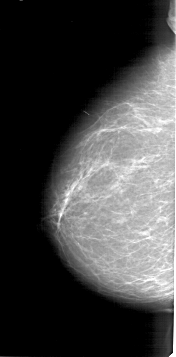

A_1403_1.LEFT_MLO

LEFT_CC LINES 6421 PIXELS_PER_LINE 3166 BITS_PER_PIXEL 12 RESOLUTION 43.5 NON_OVERLAY